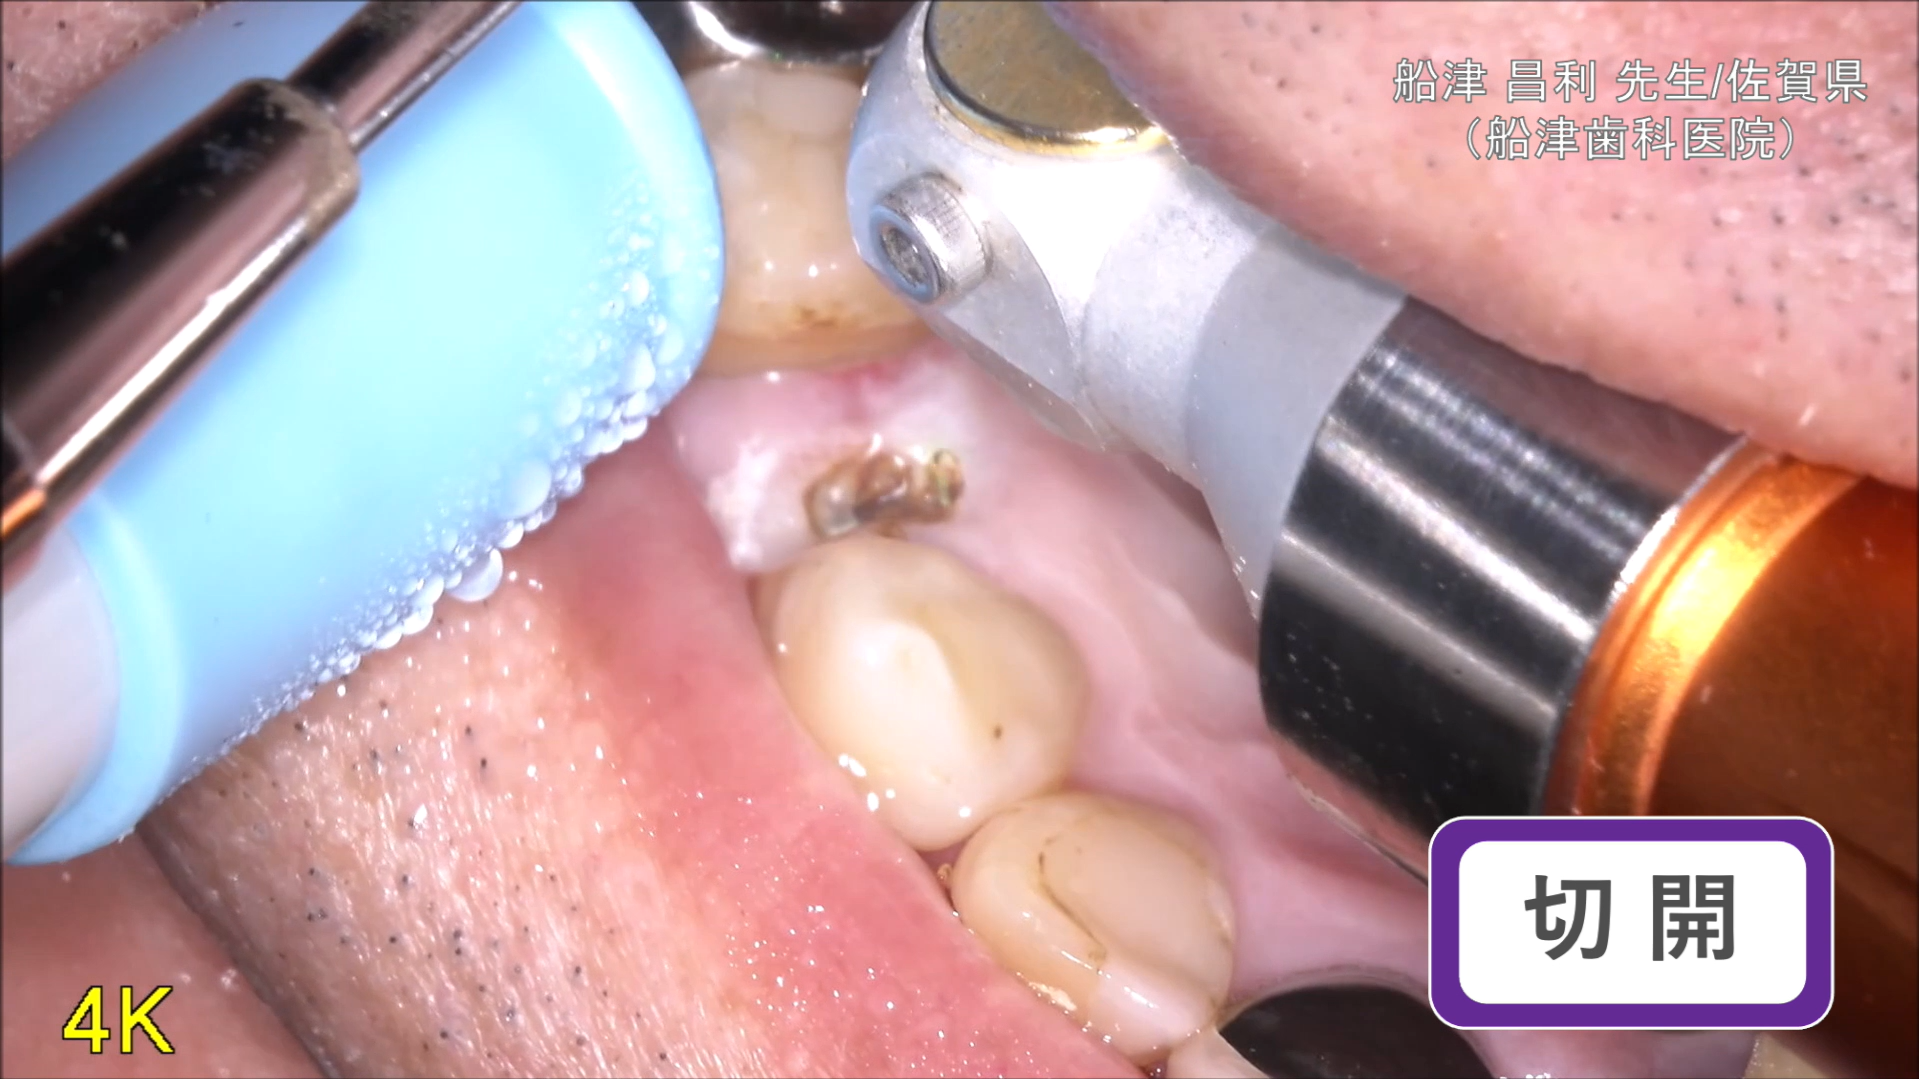

臨床例:半導体レーザーFilioを使用した先生の臨床例です。

切開